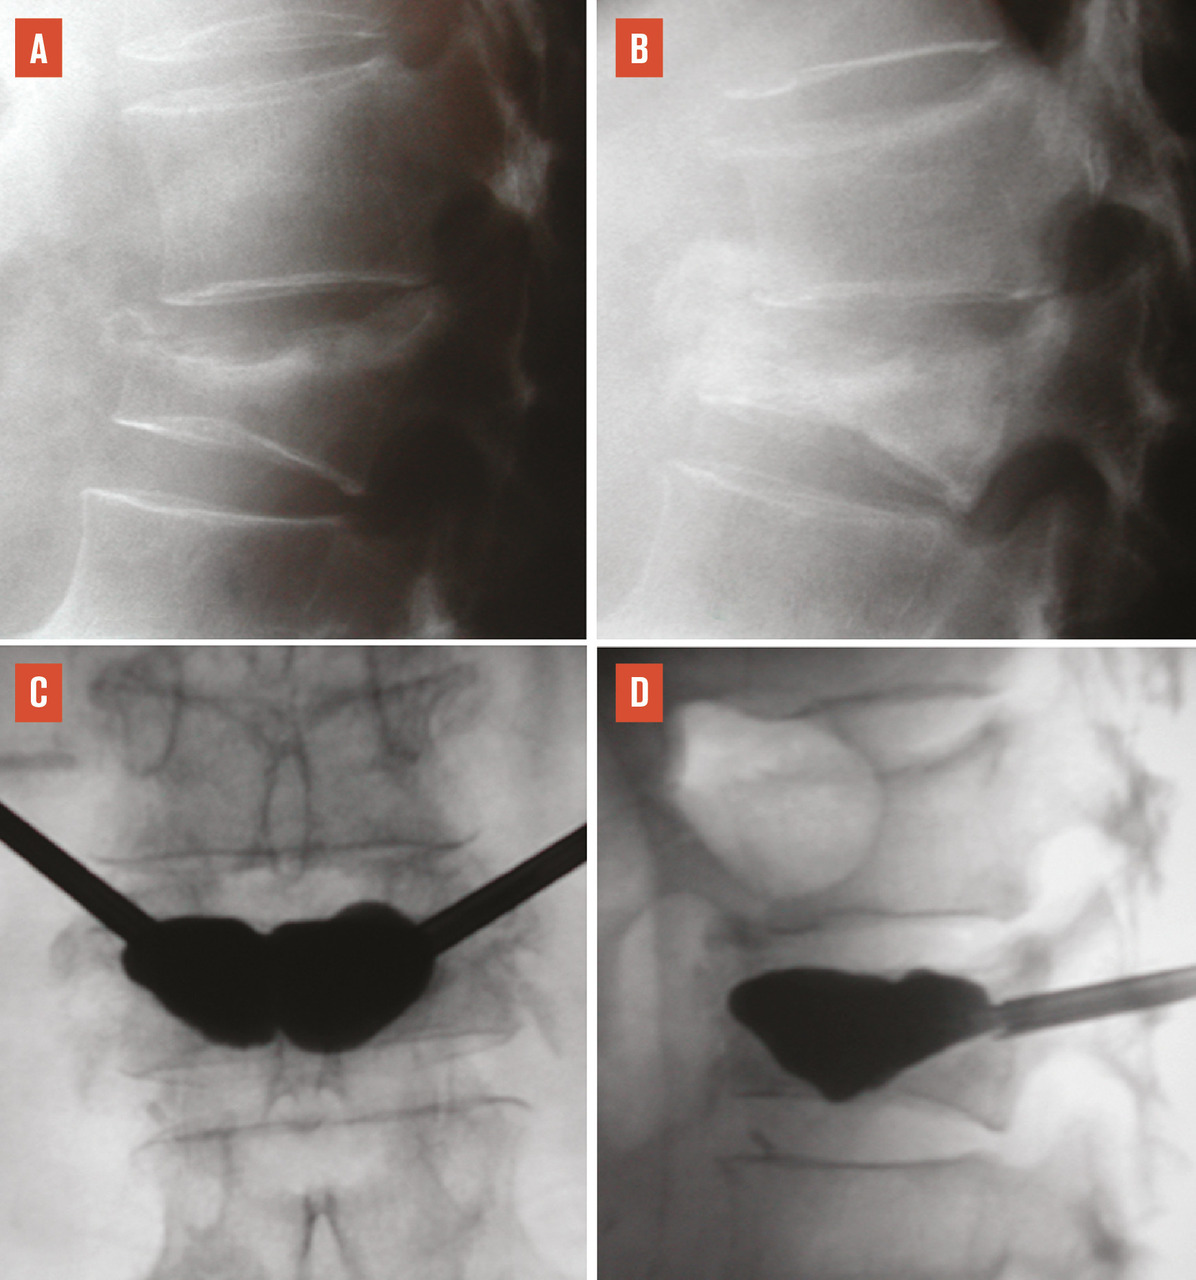

Le plus souvent, les fractures ostéoporotiques consolident et les douleurs peuvent être gérées par le ­traitement médical avant de disparaître spontanément en quelques semaines. Dans certains cas cependant, la pérennisation des douleurs requiert des morphiniques et contraint le patient à un alitement prolongé, avec les risques inhérents chez une personne âgée. La fracture peut aussi se majorer progressivement, ce qui peut entraîner une perte importante de hauteur du corps vertébral et majorer la cyphose. Parfois encore, chez le sujet âgé, la fracture ne consolide pas et une véritable pseudarthrose, avec image de « vide » (gaz) intrasomatique se constitue, source de douleurs mécaniques et d’évolution prolongée. On peut alors observer, sur les radiographies et en scanner, une image cavitaire ­linéaire intracorporéale qui peut contenir du gaz (fig. 5), ainsi qu’un signal liquidien en IRM.

Les fractures vertébrales ostéoporotiques ont tendance à se multiplier et à s’enchaîner, non seulement dans le temps, mais aussi dans le même segment rachidien, aggravant les déformations (fig. 7A et B). Dans une cohorte de femmes, d’âge moyen 74 ans, ayant une fracture vertébrale ostéoporotique récente, le risque de nouvelle fracture vertébrale dans l’année qui suit augmente de 3,6 %, si la patiente n’a aucune fracture vertébrale prévalente, à 24 % si elle a au moins deux fractures vertébrales prévalentes.24 L’âge, le caractère spontané de la fracture, la ­densité minérale osseuse, mesurée par ostéodensitométrie, les antécédents personnels et familiaux combinés dans le score FRAX25, le siège de la fracture, à la charnière thoraco-lombaire, et surtout le nombre de fractures vertébrales prévalentes permettent de prédire, dans une certaine mesure seulement, la survenue de nouvelles fractures vertébrales.

L’objectif d’une cimentoplastie ­percutanée (vertébroplastie et kyphoplastie à ballonnets) est double : antalgie et lutte contre la cyphose et le déséquilibre rachidiens. La vertébroplastie percutanée (fig. 5) consiste à injecter par voie transpédiculaire, dans le corps vertébral fracturé, un ciment acrylique (polyméthylmétacrylate) qui est de même nature que celui que l’on utilise pour sceller les prothèses ­articulaires, et dont la tolérance ­biologique est bien établie. Dans la cyphoplastie (ou kyphoplastie) à ­ballonnets (fig. 7), l’injection est précédée d’une tentative de réexpansion du corps vertébral fracturé, grâce à des ballonnets gonflables afin de regagner une partie de la hauteur perdue et de réduire la cyphose.

L’objectif premier de ces deux techniques est antalgique. Consolider le corps vertébral et soulager les patients invalidés par des douleurs, intenses et persistantes, permet leur remise en charge et la prévention des complications du décubitus. Dans les cas favorables, la consolidation de la fracture et la diminution des douleurs permettent au patient de retrouver une mobilité. La consolidation de la fracture joue un rôle particulièrement important dans les fractures pseudarthrosées avec « vide intrasomatique » (fig. 5). La ­vertébroplastie et la kyphoplastie permettent aussi d’éviter que la fracture progresse (fracture en deux temps) et que l’angle de cyphose ­augmente, ce qui est fréquent. Elles réduiraient aussi la surmortalité associée aux fractures vertébrales.23